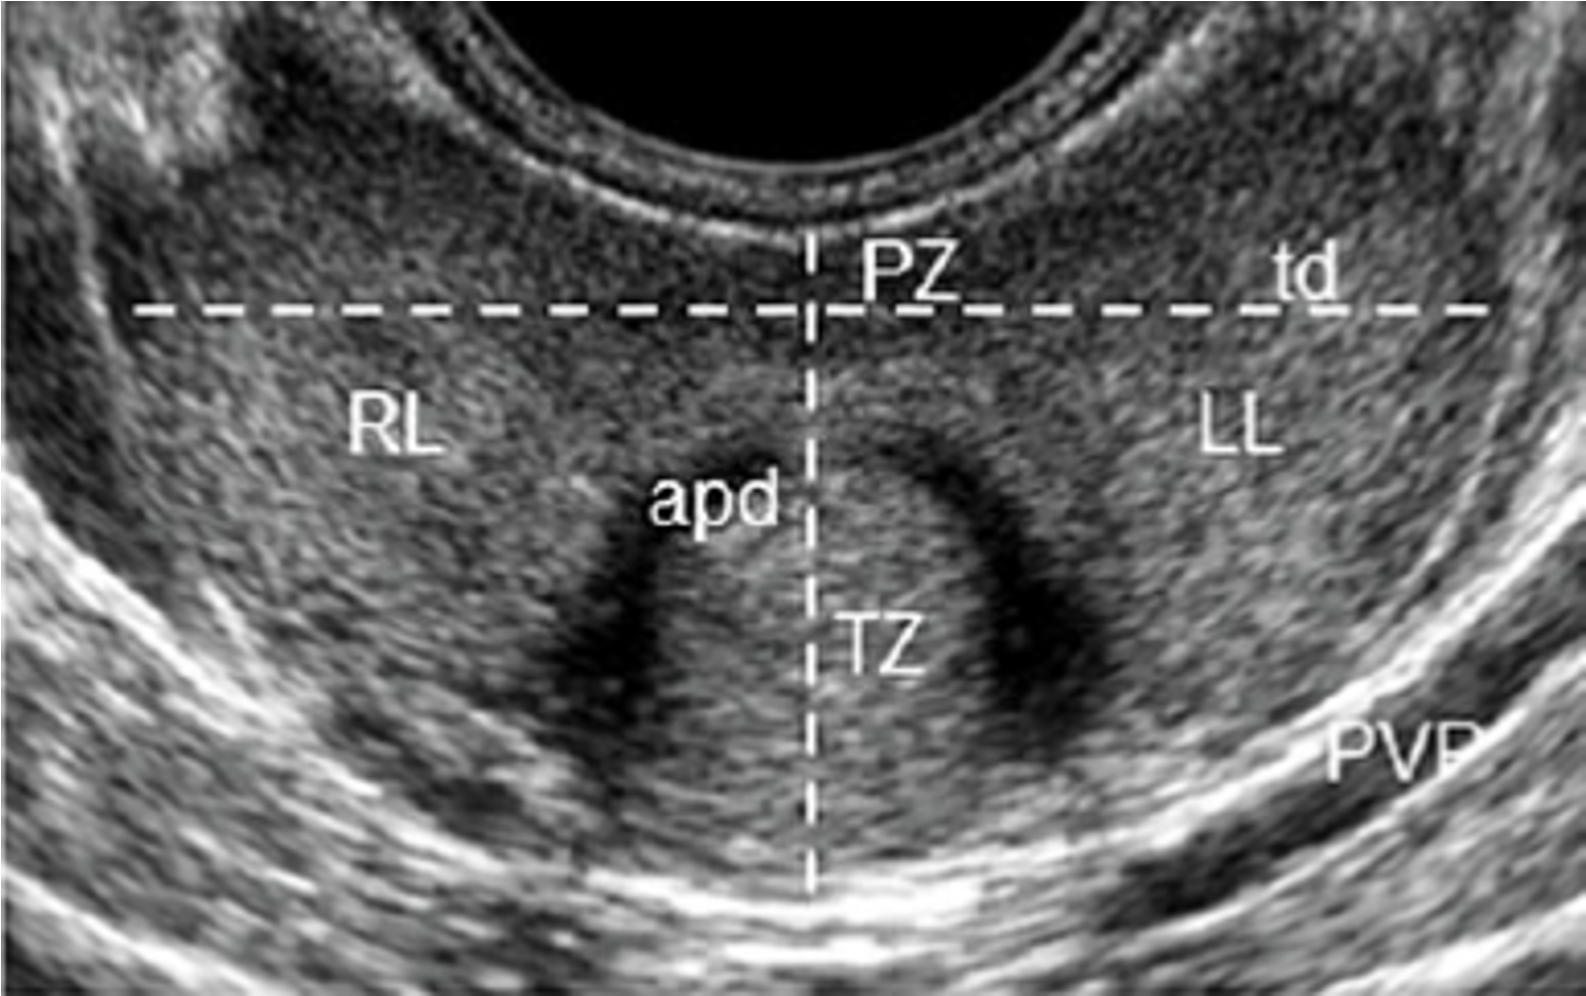

LE GHIANDOLE SESSUALI ACCESSORIE

Le vescicole seminali, situate nello spazio tra il retto e la vescica al di sopra della prostata, sono strutture tubulo-spirali, che terminano fondendosi all’ampolla deferenziale. Il lume vescicolare è rivestito da epitelio colonnare, la cui secrezione rappresenta il 70% del volume dell’eiaculato e contiene fruttosio e le proteine responsabili della formazione del coagulo spermatico.

La prostata è una ghiandola a forma di castagna, situata alla base della vescica, che avvolge l’uretra nella sua prima parte. Ha una struttura ghiandolare e fibromuscolare e secerne un liquido che nell’uretra prostatica si mescola, al momento dell’eiaculazione, alla secrezione vescicolare e agli spermatozoi epididimari. Il secreto prostatico è ricco di bicarbonati per neutralizzare l’acidità vaginale e contiene enzimi fibrinolitici che degradano il coagulo spermatico.